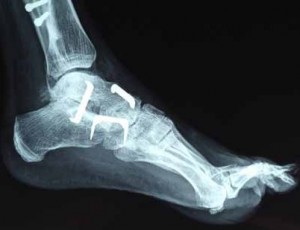

Ayak parmağı kemik çatlağı tedavisiAyak parmağında bulunan kemiklerin kırığı ya da çatlağı ağrı veren bir durumdur.

Ayak parmağı kemikleri çarpma, darbe alma, burkulma veya spor yaparken ters hareketleri sonucu çatlak oluşur. Daha ağır darbelerde ise kırık meydana gelir. Çatlaklar başlamış olan kırığın sonuca ulaşmamasıdır. Bazen kemik boydan boya değil de yarıya kadar ayrılır. Tam kırılma oluşmayan durumlara çatlak denir.

Çatlakta da basit kırık tedavi prensipleri geçerlidir. Yani çatlayan kemik alçıya alınır ve doktorun tavsiye ettiği süre boyunca alçıda kalır. Ancak çatlakların iyileşme süreci 3-4 hafta arasında olabilir. Çocuklarda çatlaklar kırık gibi çabuk kaynasa da tam aksine yaşlılarda kaynama gecikir. Bugünün şartlarında alçıya gerek kalmadan da çatlak tedavi edilebilir. Bileklikler veya sadece o bölgeyi koruyacak ortopedik cihazlarla çatlak tedavisi gerçekleşir. Dikkat edilecek nokta, alçılı kol veya bacağı mümkün olduğu kadar yüksekte tutmak, parmaklar uyuşmasın ve şişmesin diye sık sık onları hareket ettirmek gerekir.